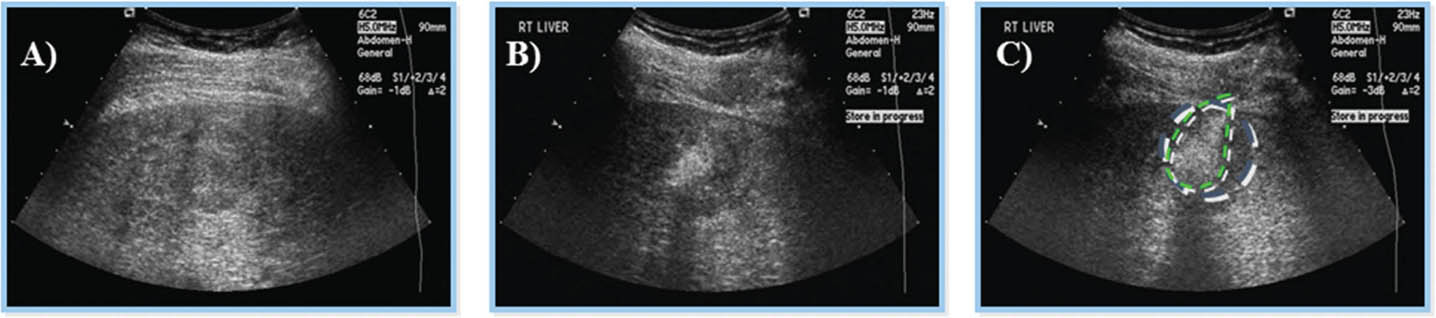

Fig 8

Figure 8. Ultrasound-guided percutaneous alcohol injection of hepatocellular carcinoma. A and B. Under image-guidance by US, administration of ethanol (97%) is performed into the tumor. C. Noting an enlarging hyperechoic signal. Although the procedure in well-trained hands is reliable and practical for large scale application, malignant recurrence rates are high.